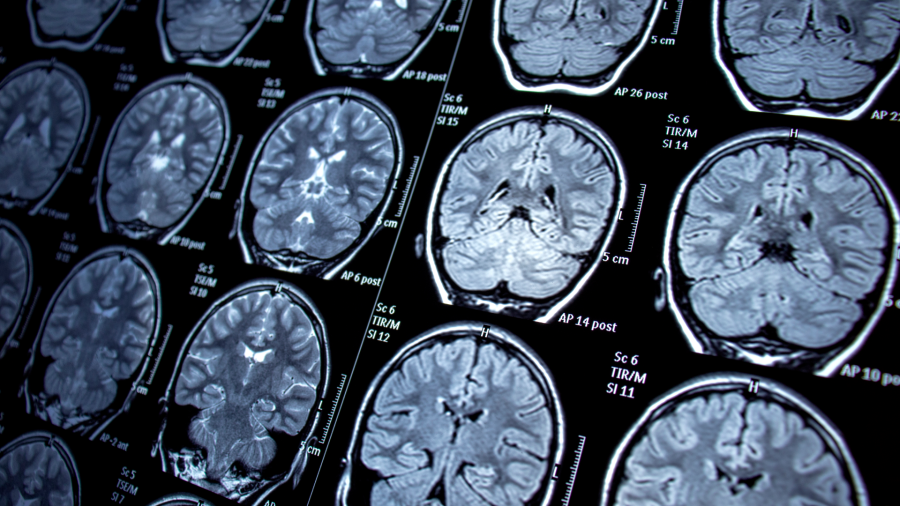

Manyetik Rezonans Görüntüleme (MRI) İcadı (1977): Raymond Damadian tarafından icat edilen MRI, vücudun iç yapısını ve işlevini ameliyatsız bir şekilde görselleştirmeyi sağlayarak, tanısal tıpta devrim yarattı.